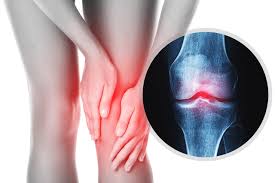

Knee Osteoarthritis

Osteoarthritis

Arthritis

Knee Fracture